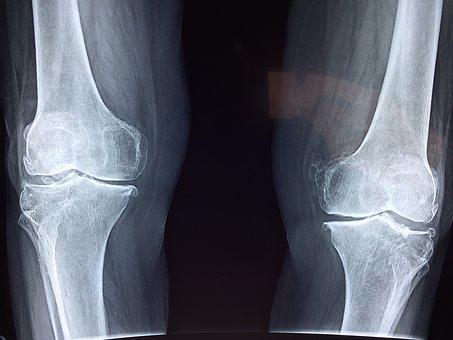

무릎 관절 문제가 더 이상 어르신들의 문제가 아닙니다. 식습관의 변화와 격한 운동으로 3040세대도 문제를 겪는 분들이 많이 있으십니다. (그게 바로 접니다.) (다들 서랍에 손목 보호대 하나 씩 있으시죠?)

- 연골은 뼈와 뼈 사이에 위치해있는 물질로 마찰을 줄여주는 쿠션 역할을 합니다.

- 체내에 콘드로이친이 감소하면 연골 변성과 노화가 빠르게 진행됩니다.